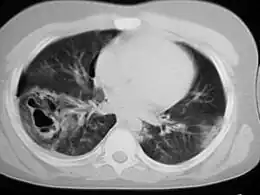

Une tomodensitométrie thoracique révélant des contusions pulmonaires, un pneumothorax et des pseudokystes